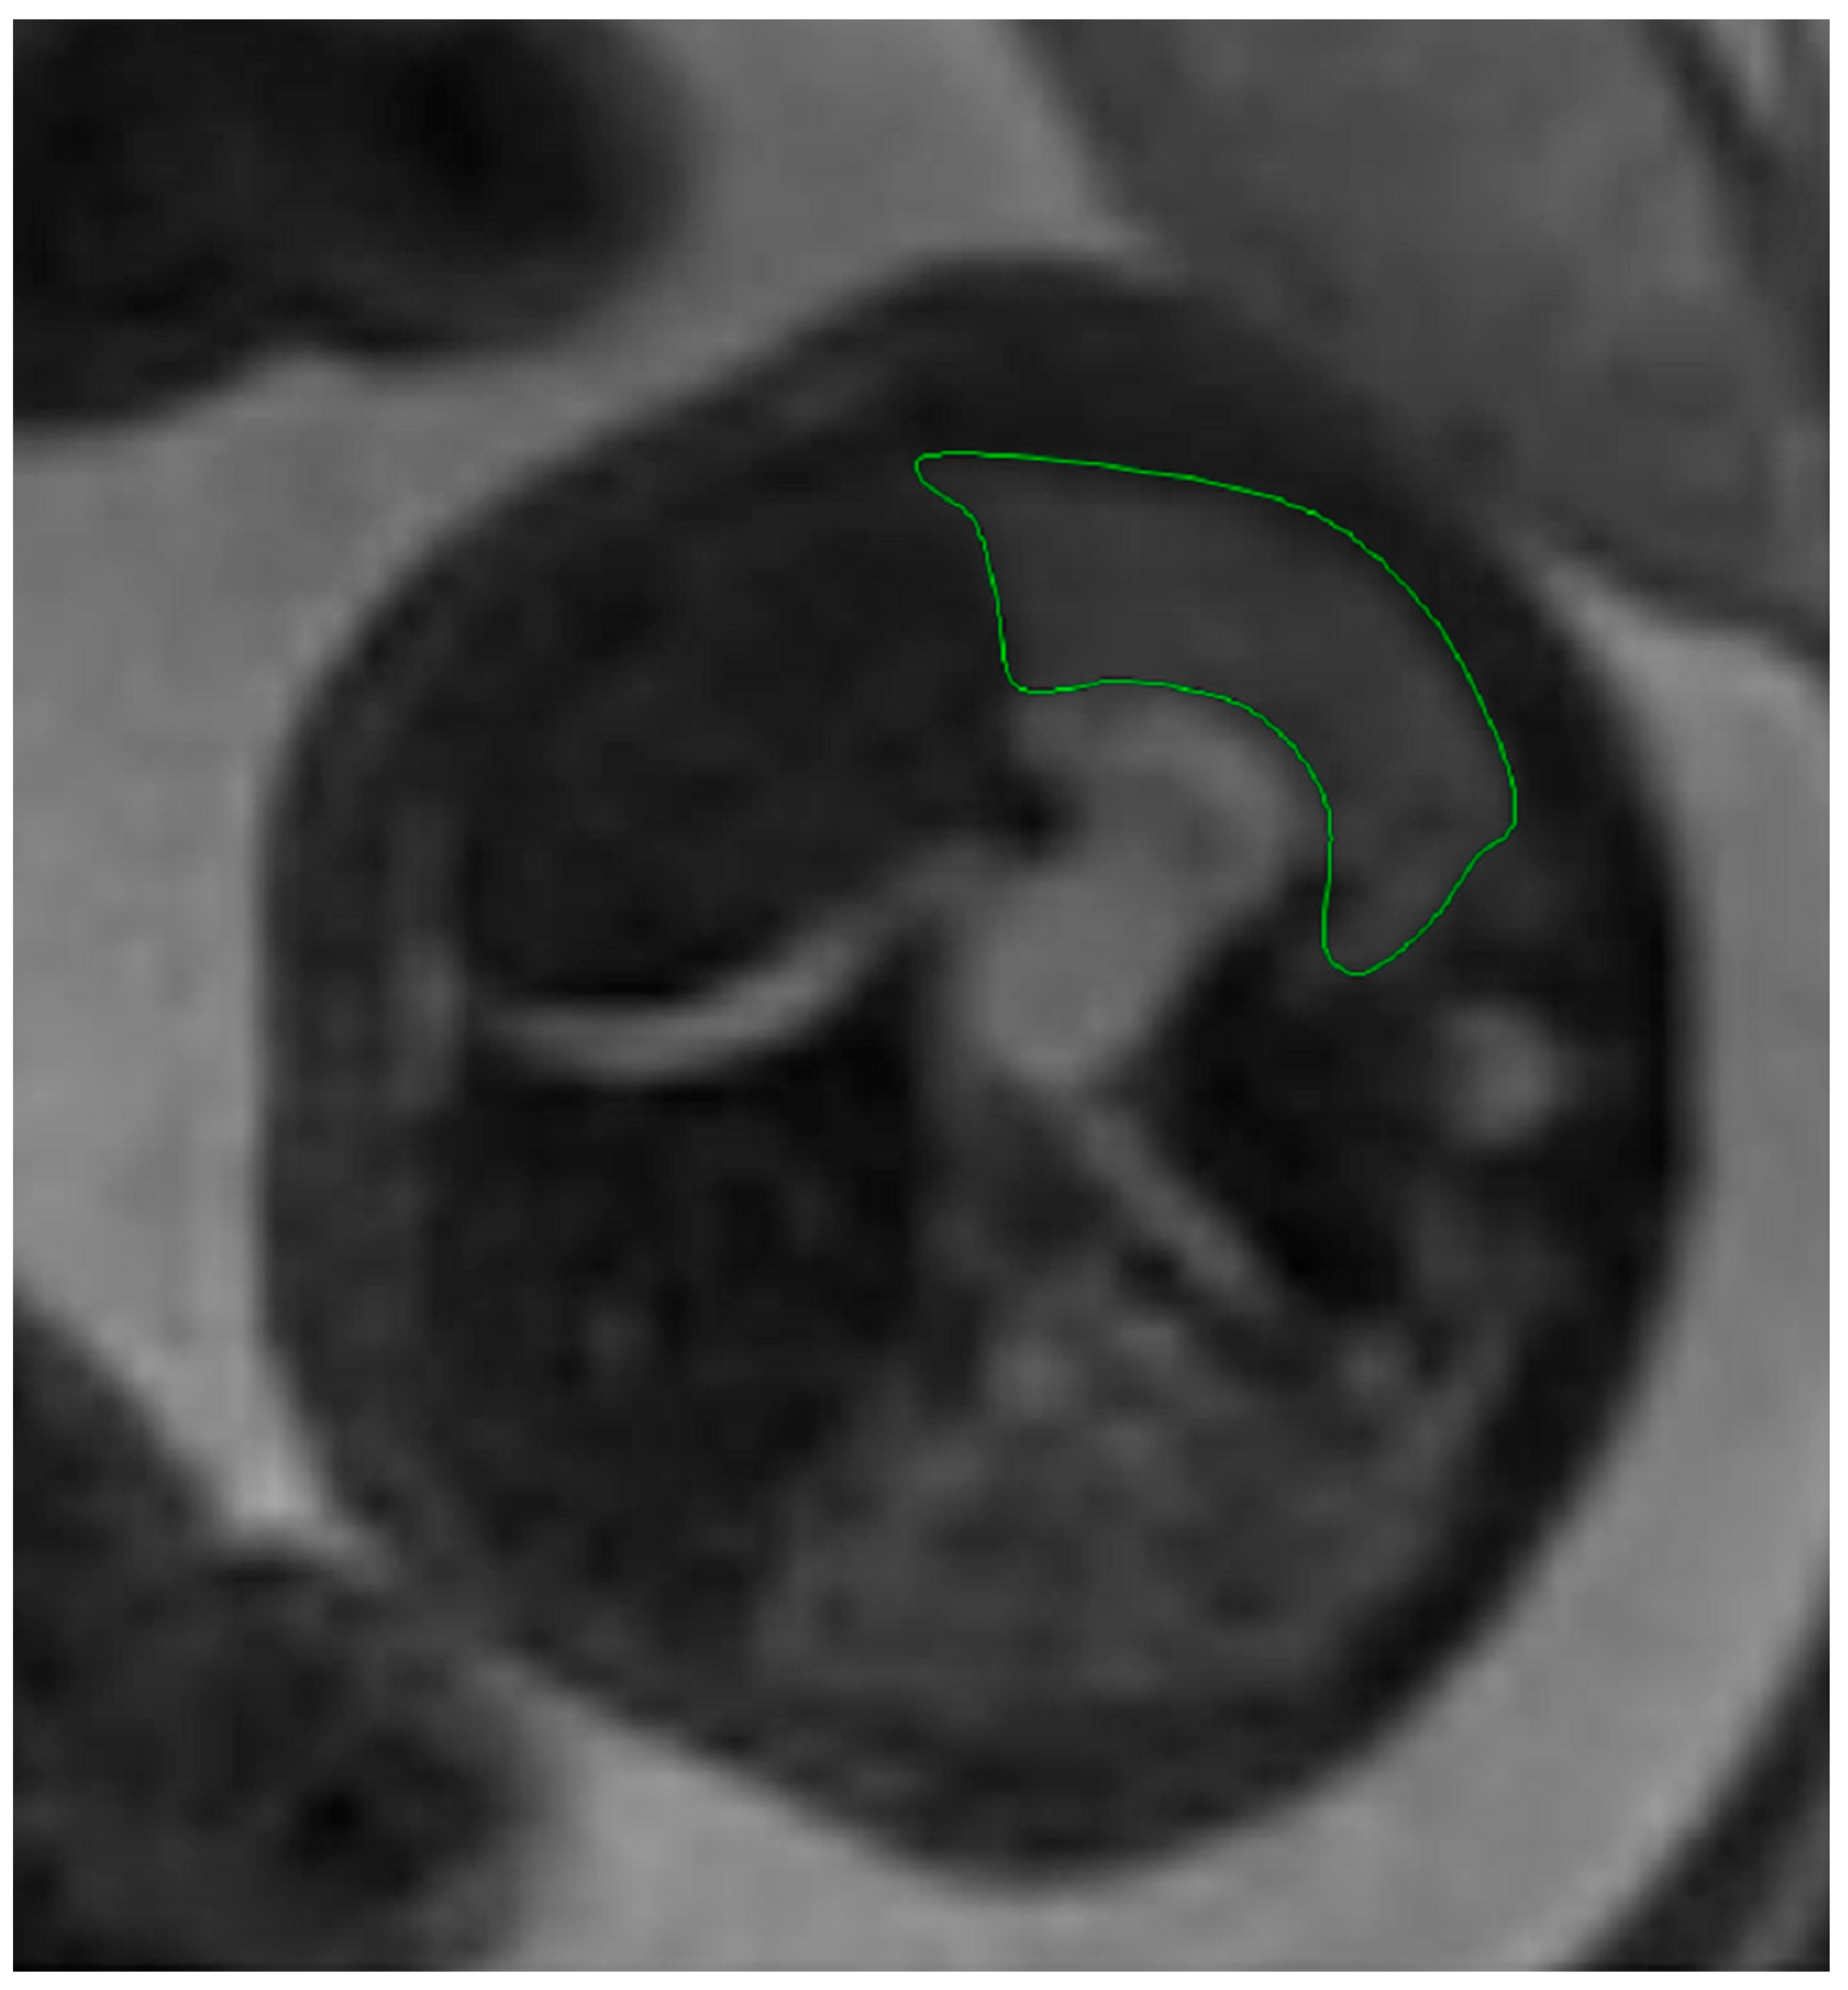

Fetal lung volume was calculated by using a new method to reduce the overestimation of the lung volume. The first step was tracing the lung area of both lungs on each slice. We then obtained the mean between every 2 consecutive slices and multiplied the value by the distance between them. Finally, we calculated the sum of all these values and obtained the TLV for each lung. For easier viewing of this parameter, we calculated the total lung volume ratio (TLVR) by calculating the ratio between our observed value and the expected lung volume values obtained from reference articles that measured standard values for lung volumetry using MRI. To be more precise, we looked at the studies of Meyers et al., Rypens et al., Osada et al., and Sefidbakht et al. [16,17,18,19] and calculated a mean from them that was used as our reference. Figure 1 and Figure 2.

Figure 1. MRI axial T2 weighted image of the fetus showing the tracing method for calculating the lung volume, using the RadiAnt DICOM Viewer program, version number 2022.1.1. The green line represents the lug area on the nonherniated side.